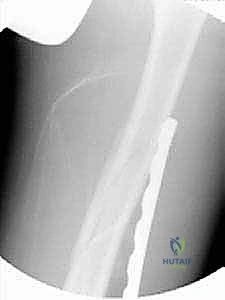

TECH FIG 4 • H,I. Postoperative AP radiographs of the long oblique proximal-third femur fracture managed with the submuscular plate.